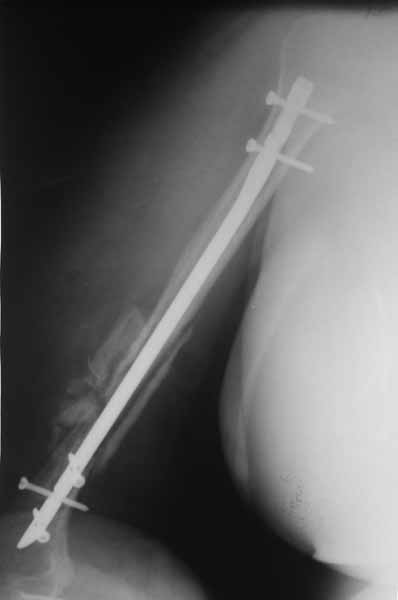

После БИОС